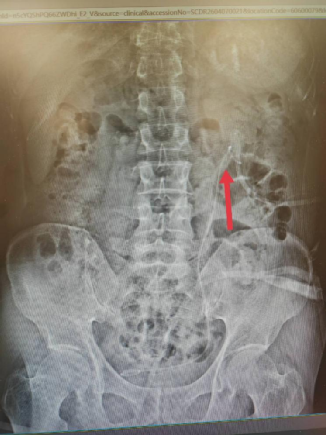

术后腹部平片:

该患者结石经成分分析确诊为“一水草酸钙结石”,为后续个性化防复发治疗提供了精准依据,也充分彰显了我科“泌尿系结石一体化综合治疗”的独特优势。区别于传统单纯取石模式,我科建立了从精准诊断、微创治疗、结石分析到防复发管理的全程闭环诊疗体系,针对不同成分、不同部位的结石制定个体化方案,真正实现“治已病、防未病”。